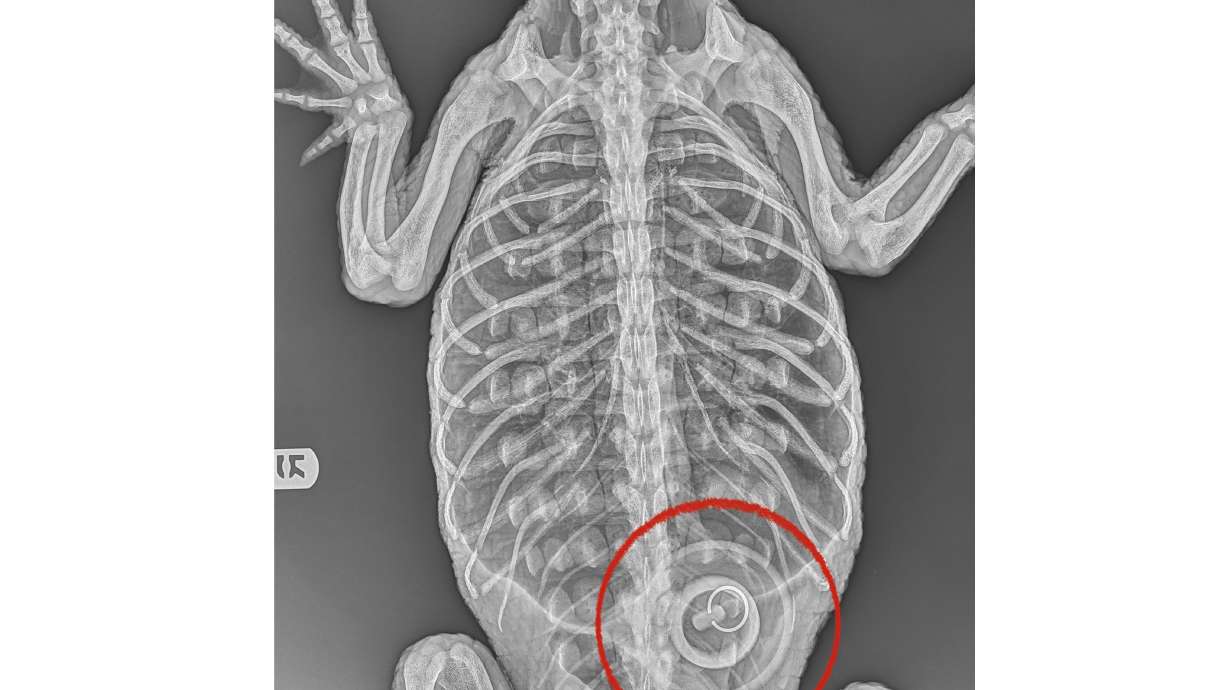

X-rays show that the alligator, estimated to be 5 to 6 years old, had ingested a 4-inch bathtub stopper, zoo officials said, noting that the animal is too weak for veterinarians to try to remove it.